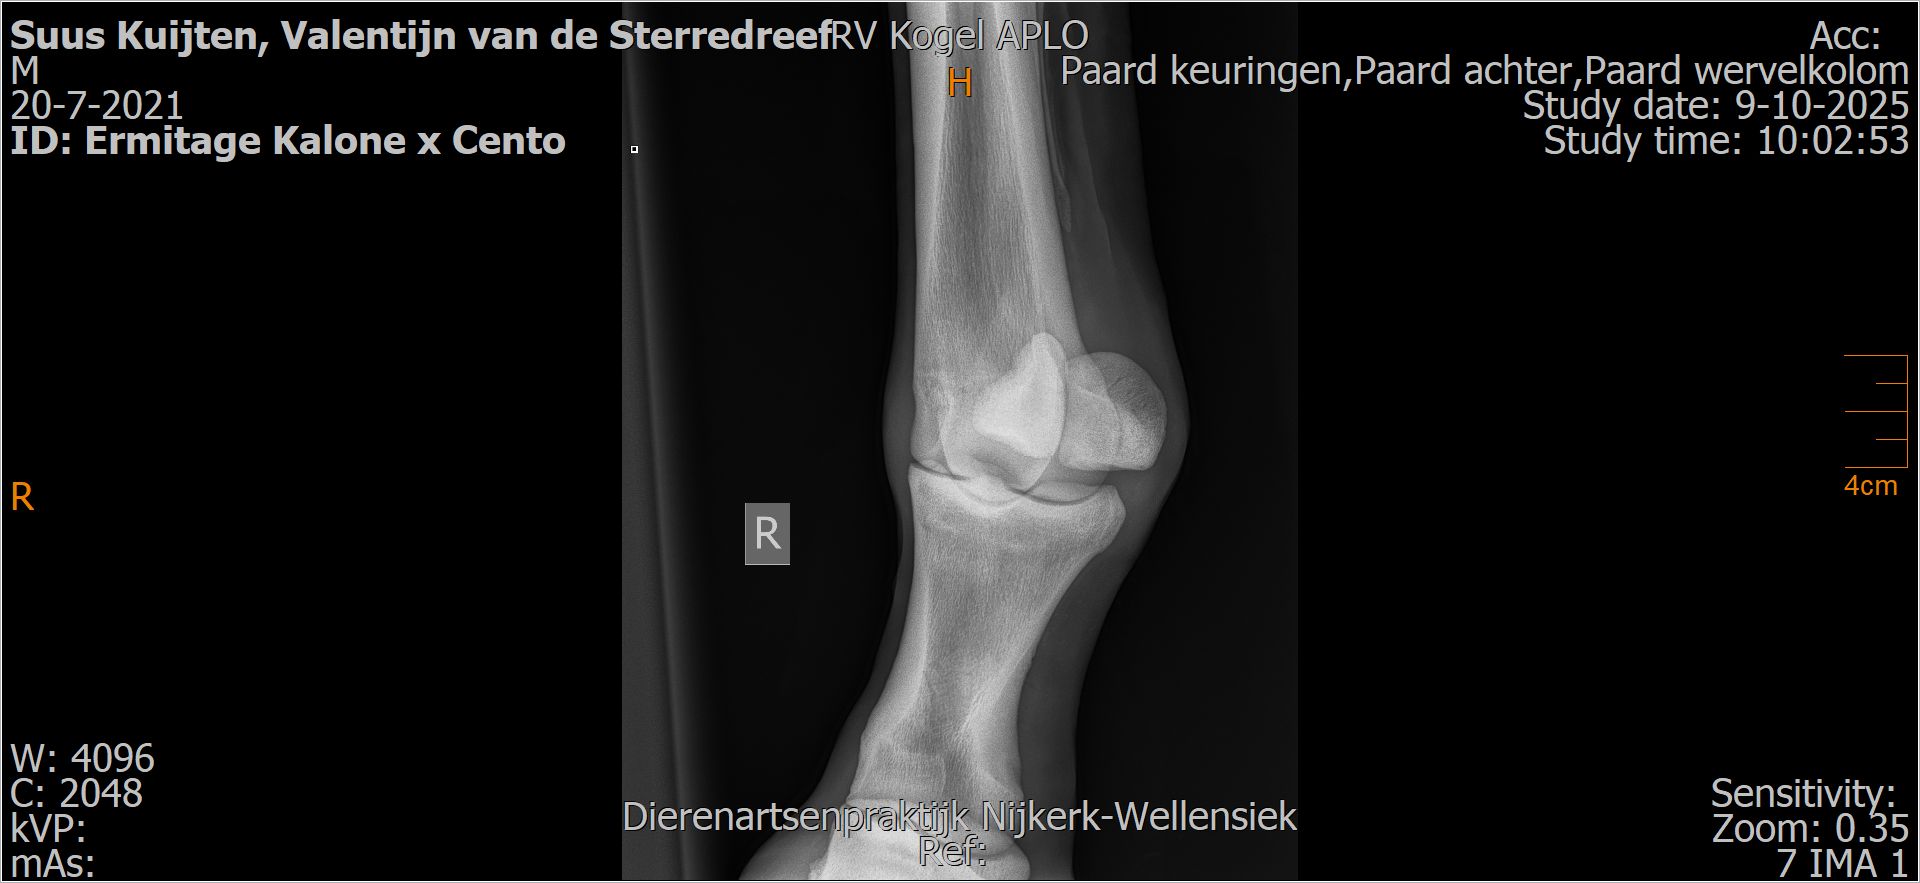

Valentijn van de Sterredreef

Röntgenfoto’s